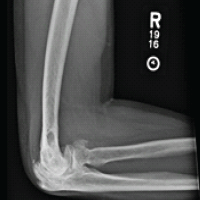

A 7-year-old boy presented with left hip pain for 1 year without any history of trauma or systemic illness. Antenatal and birth history were uneventful. Developmental history was normal. Movements of the left hip were restricted (especially internal rotation), with the left femur shortened by 2 cm. The Trendelenburg test was negative. Initial X-ray and computed tomography (CT) showed a left neck of femur transcervical fracture with a mixed area of lucency and sclerosis (predominant) in the femoral neck (Fig. 1).

Magnetic resonance imaging (MRI) showed signal intensity changes in the left femoral neck. NSA of the left femur was 115°, with Hilgenreiner epiphyseal (HE) angle of 51° (Fig. 2), and hence, surgical correction was required [1,2,3,4].